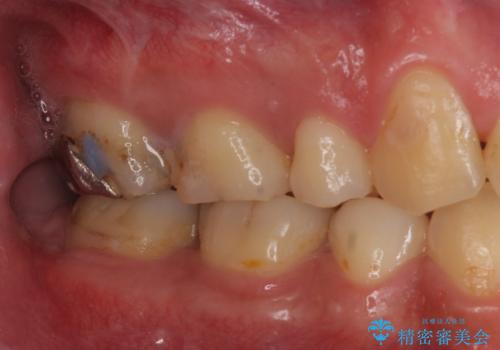

そのため、割れるリスクが少ない詰め物ではなく、被せ物による治療(ジルコニアクラウン)を行いました。

また、隣の歯も白い樹脂の下が虫歯になっており、セラミックの詰め物(e-maxインレー)による修復をしました。

- 仮歯・ジルコニアクラウン・e-maxインレー 19.8万円費用は治療当時の料金となります